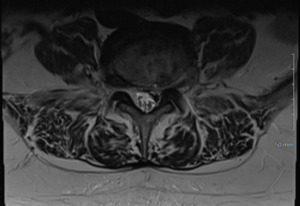

Physical examination revealed hypertonicity and tenderness in the lumbar paraspinal muscles and the left posterior hip region. He reported a pain level of 8/10 on the NPRS, reflecting both LBP and radicular symptoms. Additionally, a score of 32 out of 40 on the DVPRS indicated substantial pain-related functional impairment. A 2024 lumbar spine MRI demonstrated degenerative disc disease, arthropathy, severe left subarticular recess stenosis at L4-L5 with L5 nerve impingement, and a small left central disc extrusion at L5-S1 abutting the S1 nerve root (Figs. 1–4).

This case report documents an unexpected improvement in PLP during chiropractic treatment for LBP and radicular symptoms in a patient with a below-knee amputation. The temporary abolition of PLP reported at Visit 5, which was sustained for 2 weeks, suggests that automated lumbar long-axis distraction and myofascial release may influence the neuropathic pain pathways in amputee patients. Furthermore, lumbar distraction may reduce mechanical compression on the L5 nerve root, as seen on MRI (Figs. 1-4), potentially decreasing spinal cord hyperexcitability associated with PLP.15 Myofascial release, by addressing trigger points and muscle tension, may alter afferent input to the spinal cord, influencing pain processing.16 Chiropractic manipulation has been shown to modulate pain perception and widespread pressure sensitivity, likely through activation of descending inhibitory pathways. While these mechanisms may play a role in conditions involving central sensitization, their relevance to neuropathic pain such as PLP needs further investigation.17